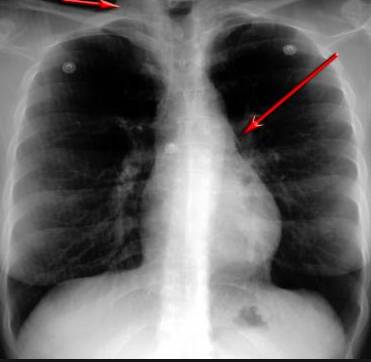

并且,因?yàn)楹粑到y(tǒng)結(jié)構(gòu)復(fù)雜,在體檢時(shí)醫(yī)生很難通過一種檢測(cè)手段,判定早期患者的病情。

使用這臺(tái)掃描儀,將直接把器官變成3D圖形!細(xì)微的毛細(xì)血管,幾毫米大的肺泡和支氣管,都將能看的一清二楚!

你的每一個(gè)氣泡,每一段支氣管,哪兒有病變都清清楚楚的將展示在醫(yī)生面前!

也就是說在一切都還沒開始惡化前,把這些有問題的器官組織都暴露的一清二楚:

空氣是如何進(jìn)入到肺部,氧氣是如何到血液,任何微小的變化都將曝露在醫(yī)生面前!更清晰的圖像,更細(xì)節(jié)的變化!

沒有這項(xiàng)新技術(shù),醫(yī)生在做體檢的時(shí)候,很難通過一種測(cè)試斷定一個(gè)人是否有呼吸系統(tǒng)疾病。

可是現(xiàn)在他們不但能看到整個(gè)肺部的3維結(jié)構(gòu)圖。還能看到空氣進(jìn)入人體后的所有微小變動(dòng)!